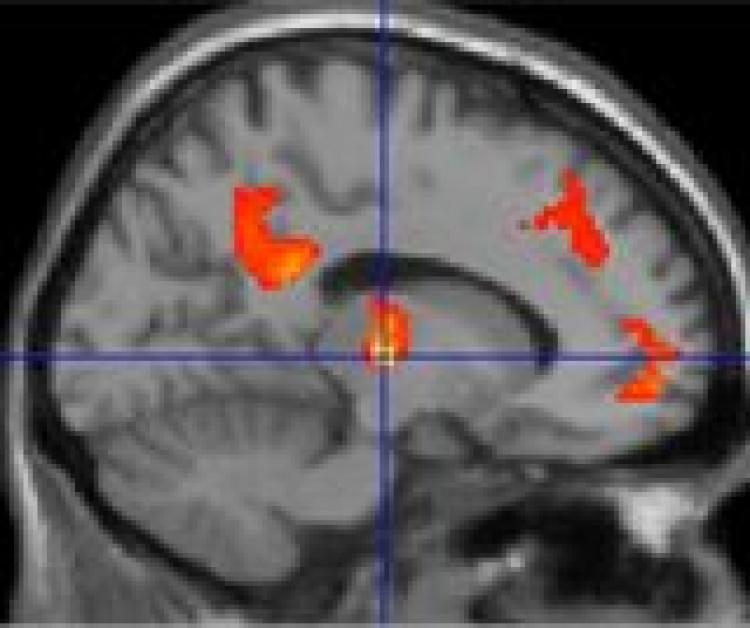

A TRANQUIL BRAIN: Researchers found that tranquil scenes can positively affect the connections between different brain regions. Michael Hunter/University of Sheffield

A TRANQUIL BRAIN: Researchers found that tranquil scenes can positively affect the connections between different brain regions. (Michael Hunter/University of Sheffield)

They found that while seeing the beach scene, the participants’ brains showed more connections between different regions than while they were viewing the freeway scene.

“Compared with scenes experienced as non-tranquil, we found that subjectively tranquil scenes were associated with significantly greater effective connectivity between the auditory cortex and medial prefrontal cortex, a region implicated in the evaluation of mental states,” the researchers wrote in their paper.

“Similarly enhanced connectivity was also observed between the auditory cortex and posterior cingulate gyrus, temporoparietal cortex, and thalamus.”